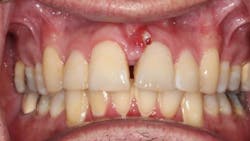

A 49-year-old male presented with pain at tooth no. 9. A labial fistula was clinically present (figure 1).